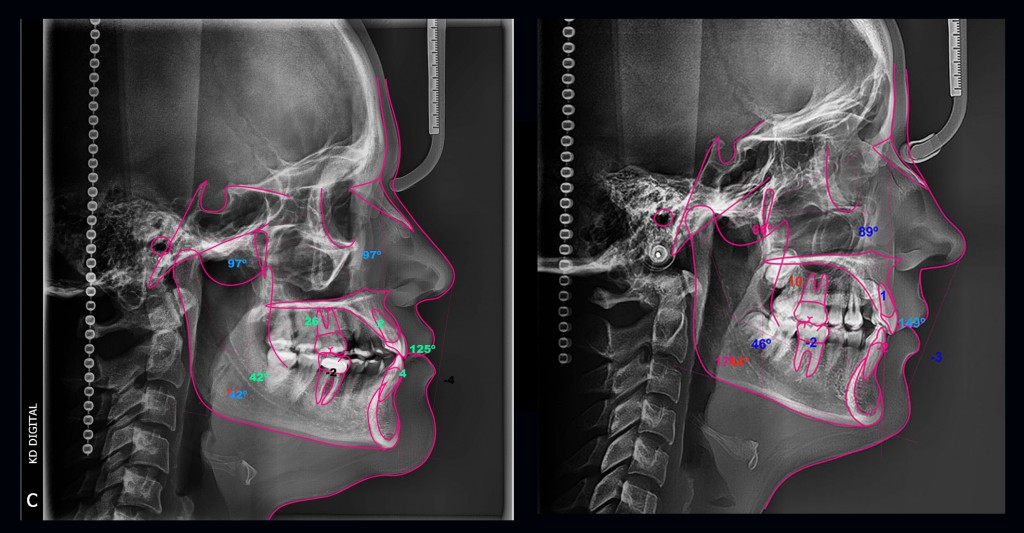

En donde algunos ven solo una radiografía, el profesional ve un mapa. El trazado cefalométrico transforma la incertidumbre clínica en decisiones estratégicas.